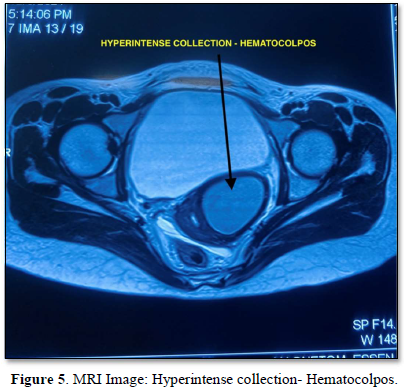

MRI also showed two separate uterine cavities with divergent apices with two cervices and single vagina, findings suggestive of didelphys uterus. There was left sided renal agenesis and hypertrophic right sided kidney (Figure 4). Hyperintense loculated collection seen in lower left cervical region suggestive of hematocolpos (Figure 5). Vaginal septum is seen on the same side. Right sided Mullerian structures were within normal limits.